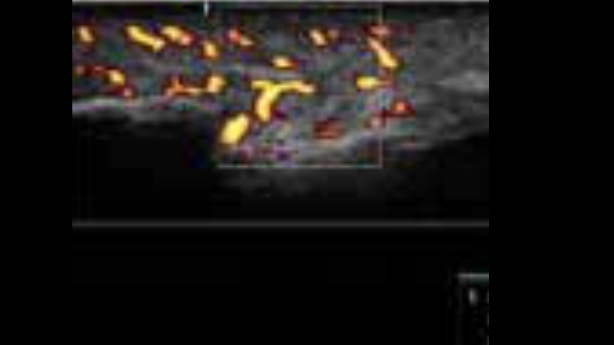

Określanie obszarów zapalnych

Ocena procesów zapalnych może być trudna. Pomiar CPP pomaga w ocenie procesu zapalnego poprzez liczenie ilości pikseli dopplera kolorowego na obrazie. Przy zachowaniu tych samych ustawień można też porównać go z wcześniejszymi badaniami.

zeus-fig3-2-4-uk

Bardziej szczegółowa wizualizacja dzięki HR Flow

Zobacz najmniejsze naczynia, nawet w opuszku palca. Tryb HR Flow umożliwia to dzięki bardzo wysokiej czułości.

zeus-fig3-3-1-uk

• zeus-fig5-2-3-uk

Doppler mocy – opuszka palca